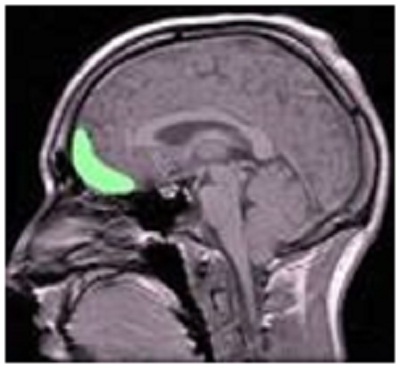

– Máy cộng hưởng từ (fMRI) được sử dụng để chụp hình não bộ lúc người thực hành Thiền, như hình dưới đây:

Lúc Thiền, định được tâm, vùng liên hệ đến sự tập trung chú ý (self-awareness), phía trên bộ não, tăng trưởng làm cho con người dễ tập trung thay vì nghĩ lung tung. Vùng thứ hai liên hệ đến an lạc vui vẻ, yêu đời (compassion) cũng được gia tăng, con người cảm thấy nhẹ nhàng an lạc thay vì chán nản giận hờn lo âu, cau có. Và đặc biệt hơn là, vùng thứ ba liên hệ đến căng thẳng (stress) bị teo nhỏ lại. Lúc con người không bị cẳng thẳng hay có rất ít căng thẳng thì sẽ không có hoặc có rất ít bệnh tật.

Trong bài “Làm sao mà Thiền có thể thay đổi bộ não.” Máy chụp cộng hưởng từ (fMRI) cũng cho thấy, thiền thay đổi não bộ làm gia tăng chất xám trong vùng hải mã (the hippocampus) là vùng quan trọng làm cải tiến việc học và gia tăng trí nhớ (learning and memory).